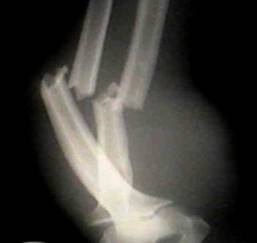

Descriptio roentgenogrammatum cum schemate

На рентгенограмі – перелом кісток лівого передпліччя в н/3 зі зміщенням уламків.

Мал. 2.

Рентгенограма кісток предпліччя при переломі обох кісток предпліччя (бокова проекція).